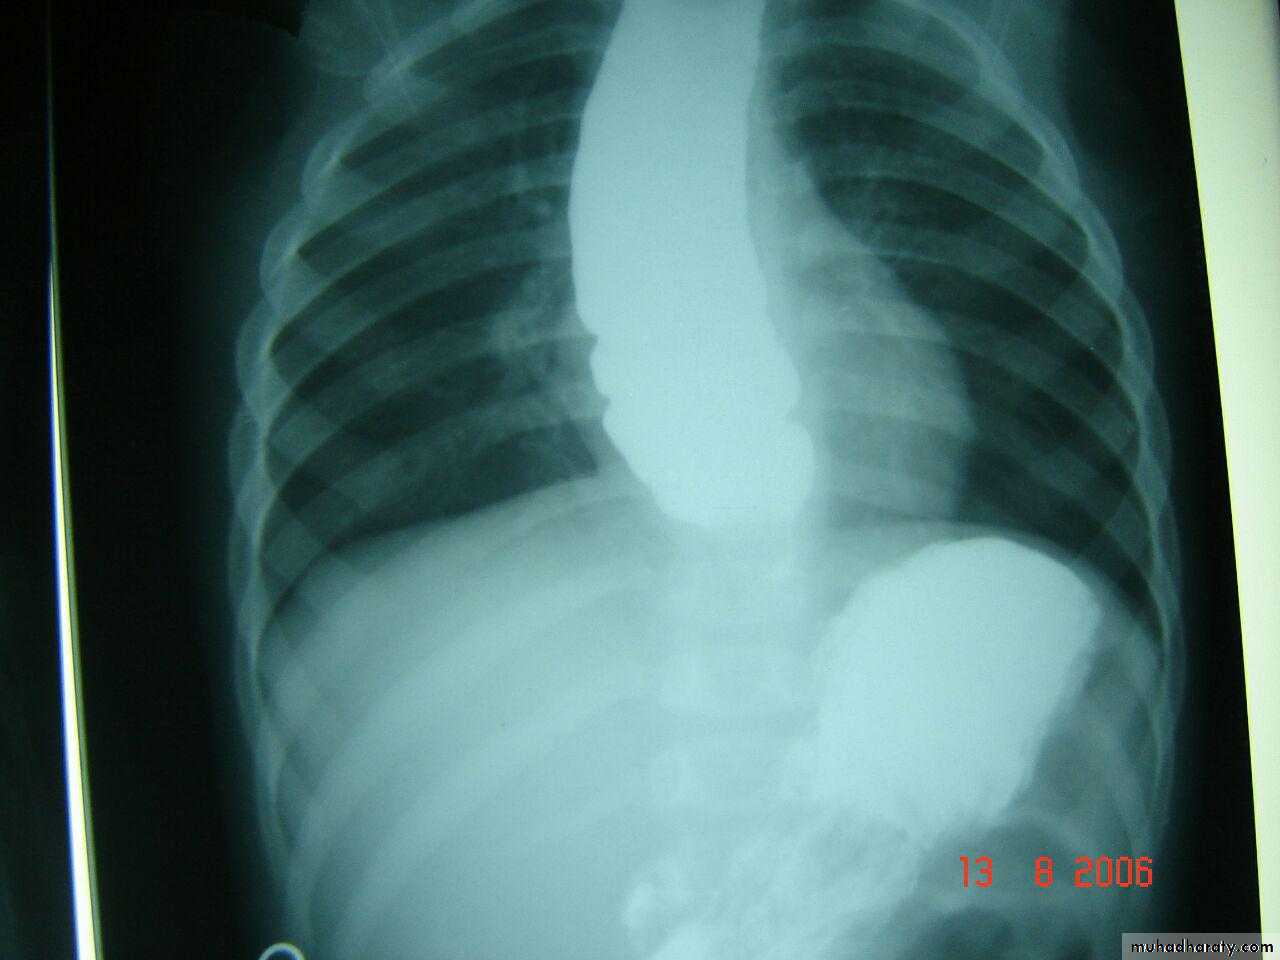

Diaphragmatic hernia

Rt. Diaphragmatic hernia or diaphragmatic eventration

Rx >> endotracheal tube and o2 and NG tubeDiaphramatic hernea and endotracheal tube

Rt. Diaphragmatic hernia (rare) + pneumothorax in lt. due to lung hypoplasia